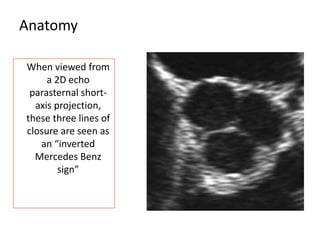

When viewed from

a 2D echo

parasternal short-

axis projection,

these three lines of

closure are seen as

an “inverted

Mercedes Benz

sign”

Anatomy When viewed from a2D echo parasternal short- axis projection, these three lines of closure are seen as an “inverted Mercedes Benz sign”